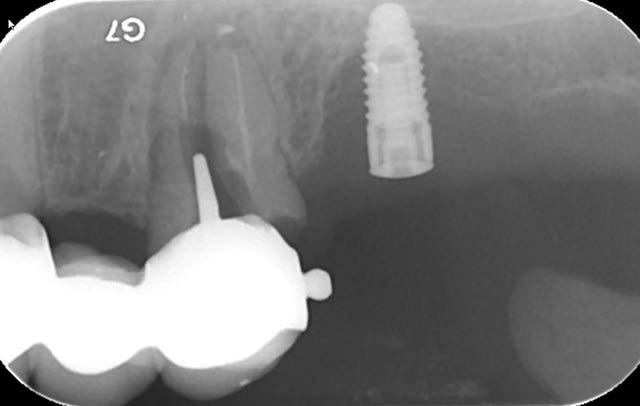

bon, c'est le cas clinique d'un pote (sera peut être plus ensuite, qui sais...) qui c'est décidé de venir me voir suite à un problème sensé être réglé par son praticien habituel au niveau de sa 12 (et 11)

j'attends les images scan pour voir l'ampleur de problème, mais c'est pas jojo...

c'est fistualisé donc c'est plus douloureux...n'empêche qu'il va y avoir du sport amha...

je pense que dans un premier temps, il va falloir aller nettoyer tout çà (et virer le cône de gutta qui dépasse) donc voie chir, obturation à rétro des 2 dents dans la séance

le passé est "lourd" sur ces dents, traitement endo, retraitements (plusieurs au moins 2 ou 3 pour chacune)

chir apicale aussi

bref, çà traine depuis un long long moment...

donc: intervention de la "dernière chance" si les images 3D sont pas trop cata...

au minimum: aller cureter tout çà + chir à rétro avec pourquoi pas comblement/membrane

le but: ne plus perdre d'os...parce qu'amha çà va se finir avec du titane....